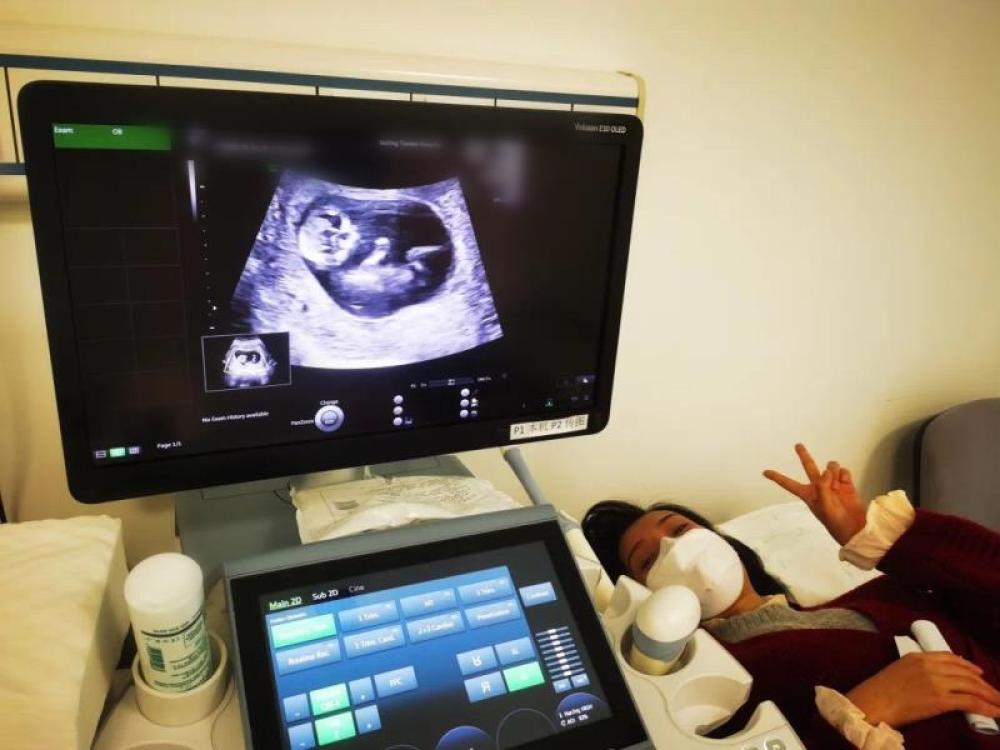

今天是我來武漢的第54天,第一次通過B超影像見到了“小家伙”。

今天一早,妻子去醫(yī)院進(jìn)行B超檢查,同事用手機(jī)拍攝下了B超顯示屏上的畫面,記錄下了這個(gè)87天的小家伙第一次“亮相”。

圖為北京天壇醫(yī)院袁磊愛人做B超檢查。

“袁磊,看看你們家寶寶,可愛嗎?”收到同事發(fā)來的視頻,第一眼就看哭了,身邊的同事看完視頻也哭了。

視頻里,這個(gè)小家伙好像聽到了外面的召喚,在媽媽的肚子里伸手、踢腿、翻身,用各種動(dòng)作進(jìn)行回應(yīng)……看到他那小胳膊小腿,一種從未有過的幸福感不停地向上涌,眼淚怎么也控制不住。

其實(shí)在武漢這么多天,他一直就是我的牽掛,今天終于看到他了,那種感受真是又緊張又激動(dòng),雖然還看不清他的樣子,但是已經(jīng)感受到他的活力。